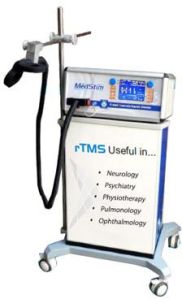

RS Enterprises is one of the noteworthy suppliers of a wide array of highly operational machines. We deal in EMG machine, ECG machine, Neuro Modulation Machine, Digital Biofeedback Machine, Therapy ECT Machine, Transcranial Magnetic Stimulation Machine, Sleep Study Machine, Pulmonary Function Test Machine, Digital Polygraph Machine, Digital Physiograph Machine, Digital Plethysmometer Machine, AD629 Diagnostic Audiometer, AD226 Diagnostic Audiometer, Channel ECG Machine, Electric OT Table and many more. As a respected name in the industry, we procure the entire range of products only from the reliable manufacturers or vendors after checking against numerous quality parameters such as functionality, maintenance, manufacturing defect, etc. We are capable of undertaking bulk as well as urgent orders as we maintain a streamlined inventory management system.